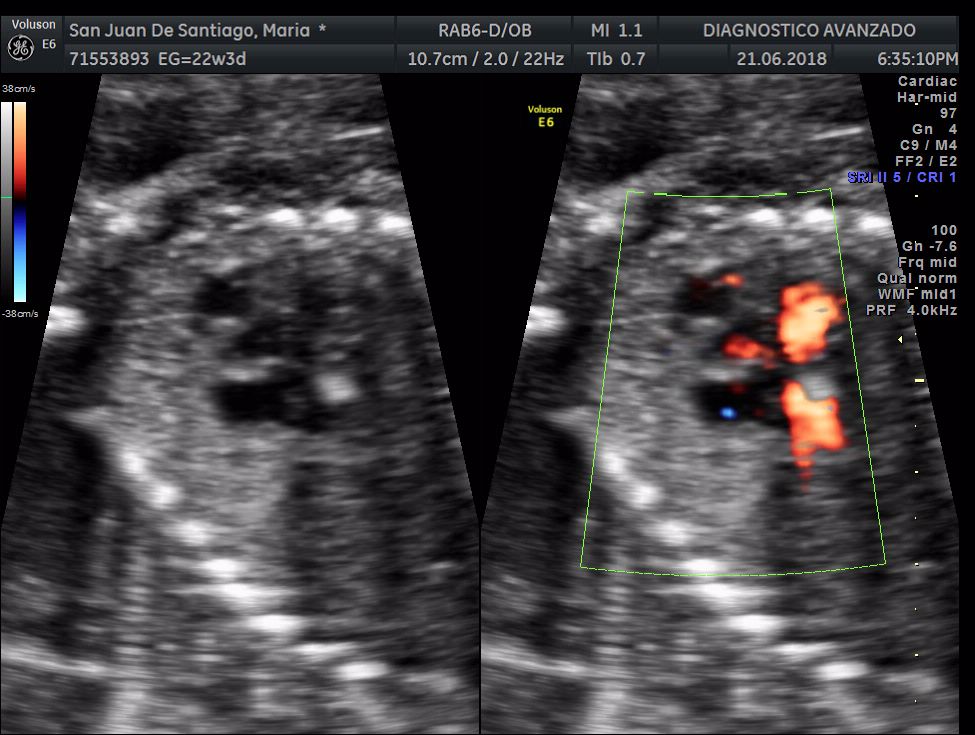

¡Hola a todos! Hoy hemos ido a hacer la tradicional ecografía 3D de la niña, os dejamos todo el material (aunque es un poco demasiado).